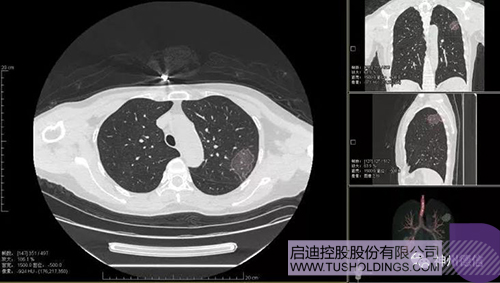

神州德信新冠肺炎检测及智能量化分析系统

jjb战略投资企业神州德信作为国内领先的肺部影像人工智能企业,针对新型冠状病毒肺炎开发了智能检测及量化分析系统,并在陕西、重庆等地定点医院投入使用。该系统在疑似病例大规模快速筛查及精准诊断方面发挥了重要作用,特别是其具有的肺炎患者临床影像跟踪量化随访功能,为快速有效阻断疫情扩散提供了有力武器。